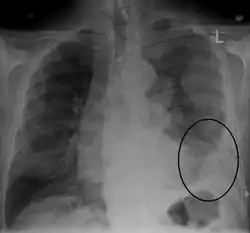

CT scan showing a left sided mesothelioma with an enlarged mediastinal lymph node | |